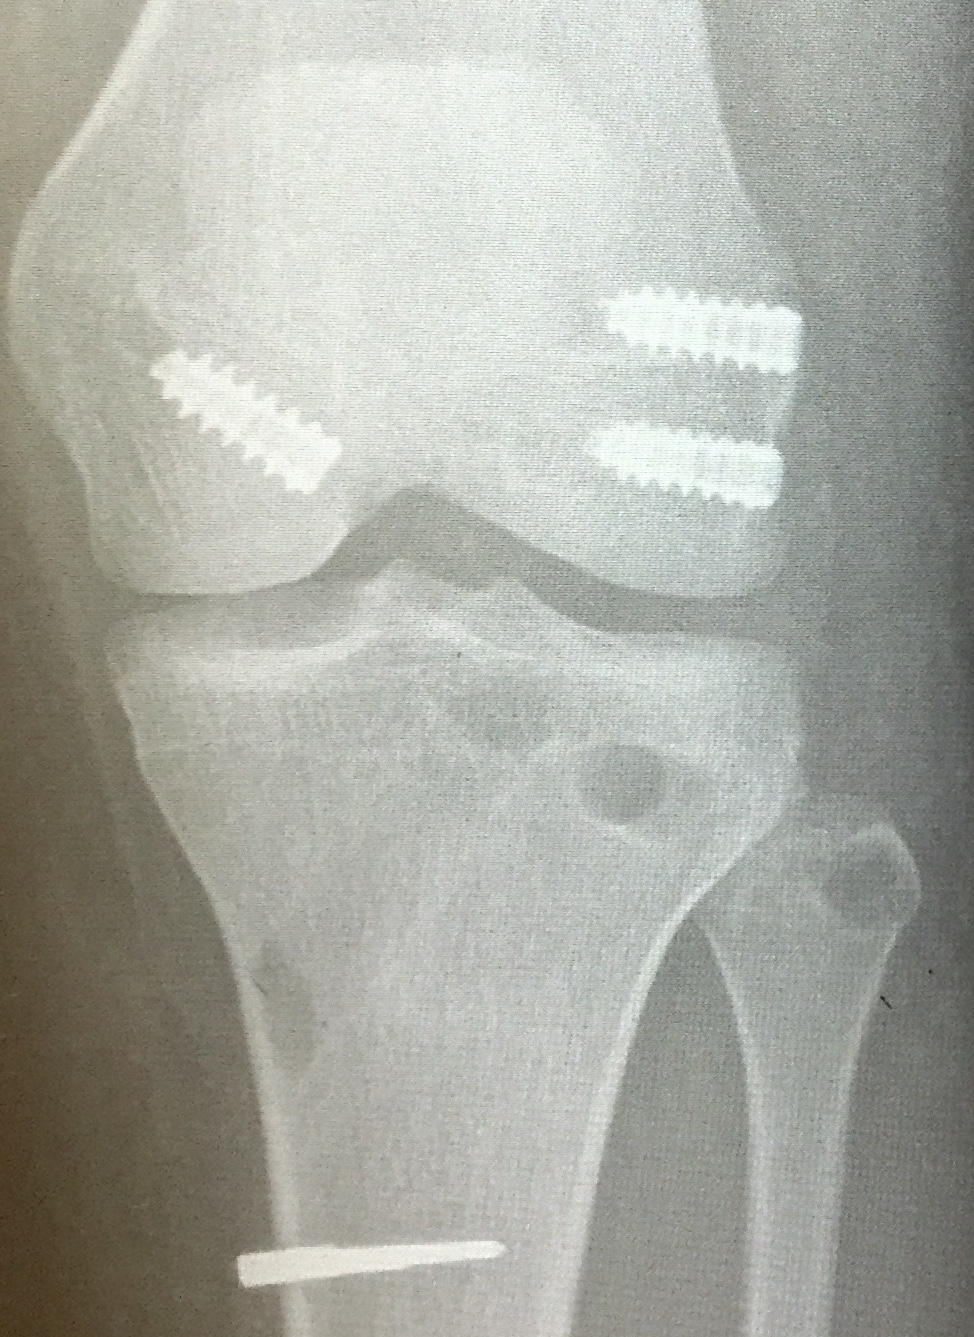

Right knee arthroscopy displaying empty medial femoral condyle. PCL jig has been placed and beath pin drilled outside in

PCL graft has been passed in right knee. ACL and PCL grafts passed

Xray following PCL reconstruction, LCL and politeus reconstruction. CT demonsrating popliteus and LCL tunnels